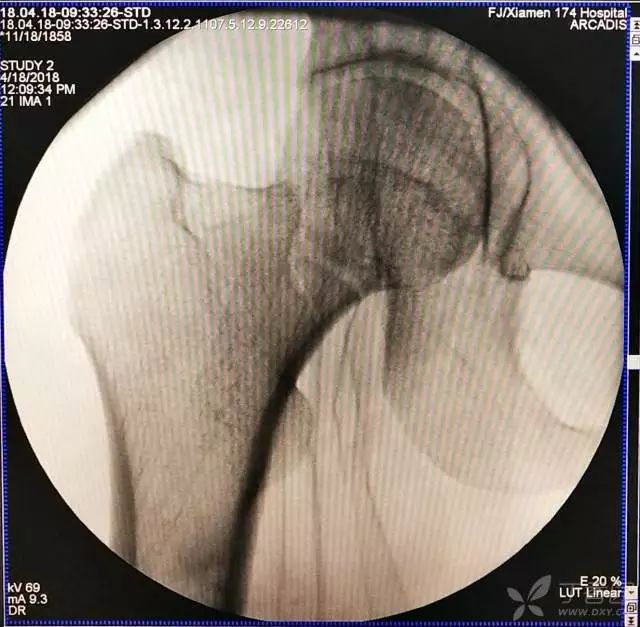

6. 然后依次打入倒品字上方的两枚导针

7. 摆 4 字位检查侧位导针的位置是否恰当

8. 最后测深依次拧入合适长度的螺钉

第一枚导针打好以后,根据该导针距离股骨颈下方的距离(如下图),确定上方两枚导针的距离,距离过近,会导致螺钉打架或者汇聚,过远则打不到股骨颈内。

打第 2、3 枚导针有个小技巧,首先用导向器套住第一枚导针判断合适的距离,以及上方两枚导针之间的距离,此时顺着导向器插入第 2 枚导针。

这里需要注意的是,不是沿着导向器直接打进去(这样往往打入的导针无法与第一枚导针平行,不好看),笔者会稍打进去一点能把针固定住就好,然后把导向器退出来,看体外针尾平行方向往里打。这样确实打出来的导针都比较平行。最后把第三枚导针按第二枚的步骤打进去就可以了。